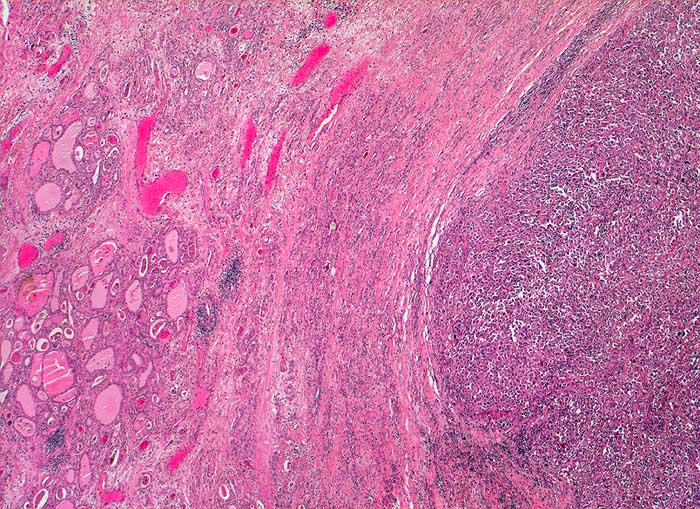

Anaplastisches Schilddrüsenkarzinom

Zwischen Schilddrüsenparenchym und solidem Tumorknoten liegt eine dicke bindegewebige Kapsel. Bereits in dieser Vergrösserung ist erkennbar, dass der Tumor weder follikuläre noch papilläre Strukturen enthält.

Strumaknoten links mit Einengung der Trachea

Histologie

Vergrösserung

25